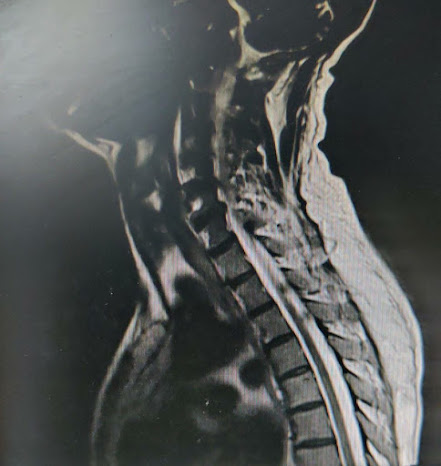

-C3-C6 OPLL that is osteomalacial changes referred for neurosurgical intervention

-SURGERY ADVISED: C3-C6 screw fixation,C3-C6 lamenectomy